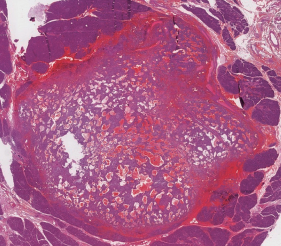

Pablo Marcos-Santos, Martín Bailón-Cuadrado, Miguel Toledano-Trincado, David Pacheco-Sánchez

|

|

|